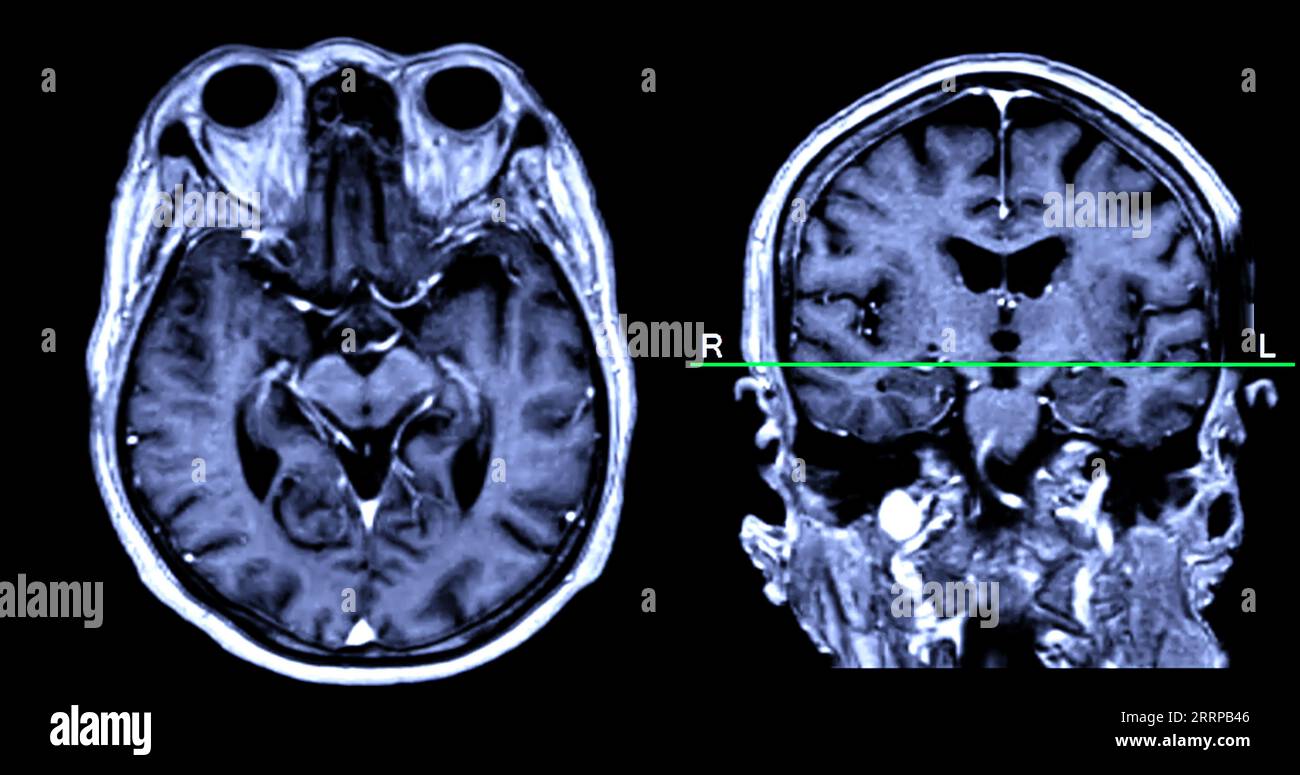

From www.alamy.com

MRI brain scan Axial and sagittal view with reference line for detect What Can Brain Mri Detect That Ct Cannot Bones, stones, blood, organs, lungs, cancer stages and abdominal emergencies. Ct scans are the most common. A variant called mr angiography (mra). An mri scan can be used to examine almost any part of the body, including the: Internal organs, such as the liver, womb. Where mri really excels is showing certain diseases that a ct scan cannot detect. Some. What Can Brain Mri Detect That Ct Cannot.

MRI brain scan Axial and coronal view with reference line for detect What Can Brain Mri Detect That Ct Cannot Understand their pros and cons along with general guidelines that doctors use to decide between head ct and mri. Ct scans are the most common. Internal organs, such as the liver, womb. Mri can detect abnormalities that might be obscured by bone with other imaging methods. Where mri really excels is showing certain diseases that a ct scan cannot detect.. What Can Brain Mri Detect That Ct Cannot.